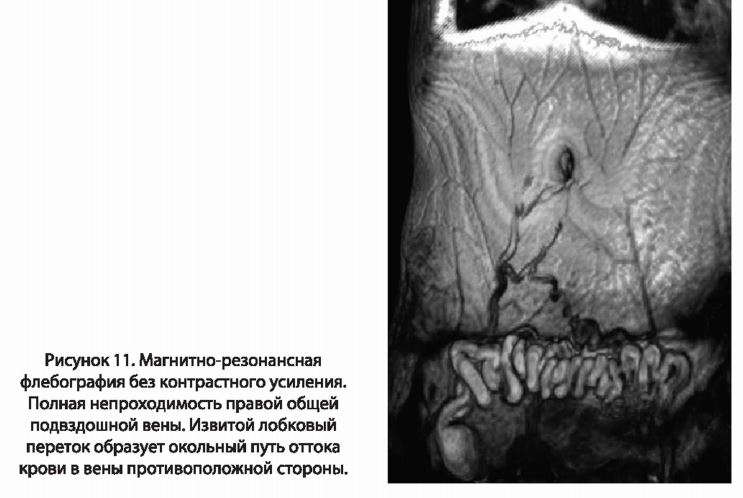

В последние годы, как альтернативу традиционной флебографии, стали применять магнитно-резонансную и компьютерную мультиспиральную флебографии (МР-ФГ и МСКГ-ФГ). Ценностью МСКТ-ФГ является тот факт, что она позволяет визуализировать артериальную и венозную фазу кровотока. Также она дает возможность одномоментно исключить тромбоэмболию легочных артерий при повторном тромбозе у больных с посттромботической болезнью. Преимущество МР-флебографии (рис. 11) перед традиционной контрастной флебографией и МСКТ-флебографией заключается в отсутствии необходимости введения контрастного вещества. Она позволяет оценить все пути оттока крови за счет визуализации низкоскоростных потоков крови.

Заболевание, как правило, начинается с проявлений острого венозного тромбоза. Среди признаков заболевания наиболее часто выявляются боль, повышенная утомляемость нижней конечности, ощущение тяжести, распирания в области голени, судороги. Наиболее постоянным объективным признаком заболевания является отек. После пребывания в постели с возвышенным положением ноги отек уменьшается, иногда остается только пастозность (незначительная отечность) мягких тканей. После пребывания на ногах к концу дня отечность, как правило, резко выражена. В процессе развития болезни изменяется характер отека. В случае односторонней окклюзии (полного закрытия просвета) подвздошной вены, часто можно обнаружить так называемый «лобковый переток»: крупную, варикозно измененную вену под кожей надлобковой области (рис.5). Этот переток позволяет компенсировать отток крови из конечности путем переброса части объема в нормально функционирующий бассейн противоположной подвздошной вены.